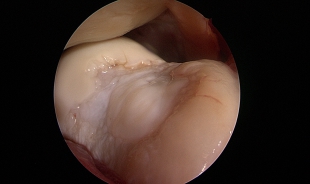

- Arthroscopy of the knee joint

- Meniscus operations

- Removal of free joint bodies